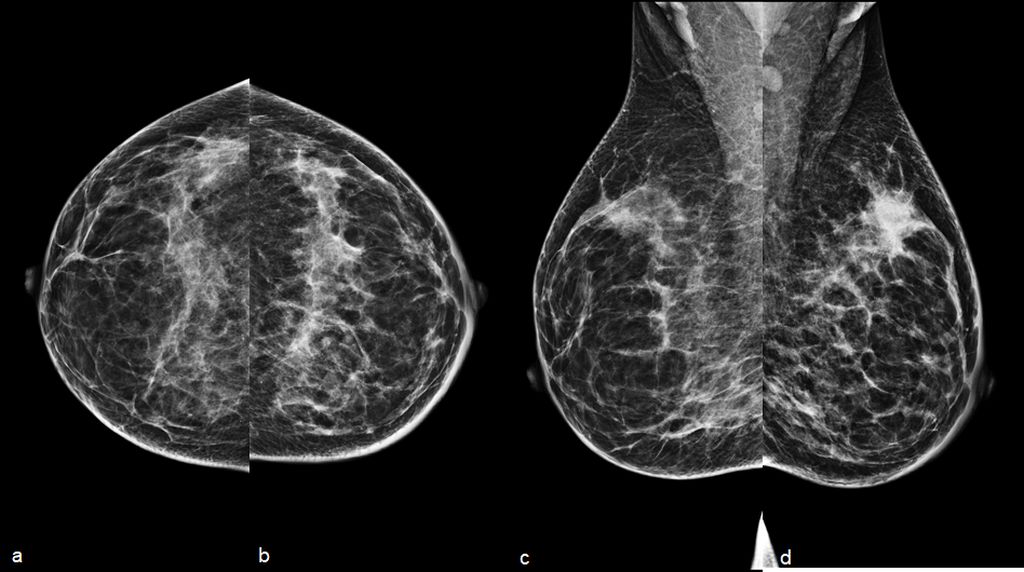

A 34-year-old woman presenting with a painless palpable right breast l...

Read More